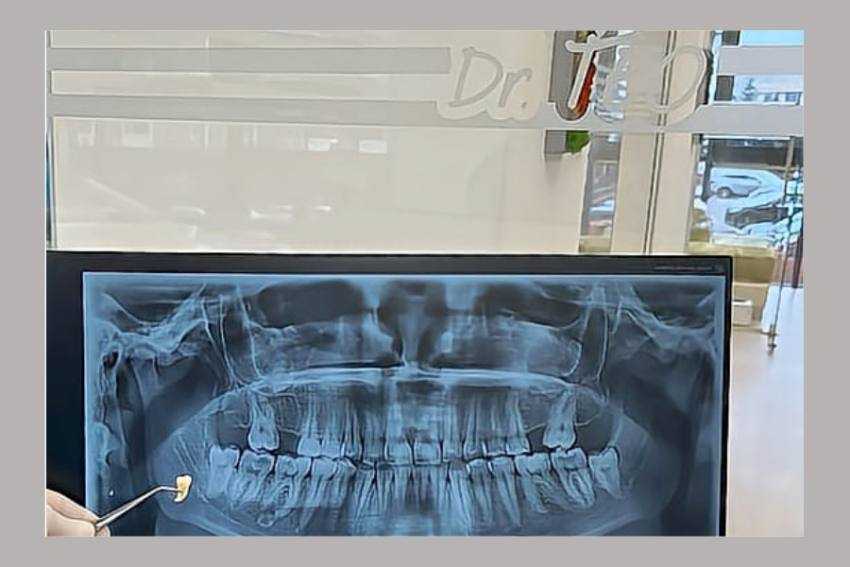

Deși, în trecut, extracția dentară era o practică foarte uzuală, recurgându-se la ea de fiecare dată când pacientul resimțea o durere acută la nivelul dintelui, în prezent, datorită evoluției medicinei stomatologice, medicii încearcă pe cât posibil să salveze dintele afectat.

Există și cazuri în care extracția dentară este singura soluție:

- În cazul unui dinte puternic afectat de carie care nu mai poate fi restaurat prin obturație ori mijloace protetice. De amintit este că procesul carios poate afecta inclusiv un dinte stâlp aflat sub o lucrare protetică

- Dinții afectați de parodontită marginală cronică profundă (boala parodontală) care prezintă mobilitate severă, de gradul al III lea

- Dinte cu gangrenă ori procese supurative repetate care pot afecta alți dinți din vecinătate

- În cazul fracturilor corono-radiculare, atunci când linia de fractură implică coroana, dar și rădăcina dintelui în cauză.

- Extracția în scop ortodontic. Spre exemplu, molarii III (măselele de minte) pot împiedica alinierea celorlalți dinți pe arcadă în cazul unor înghesuiri dentare, iar dinţii incluşi pot provoca dizarmonii dento-alveolare, pot împiedica erupţia sau redresarea ortodontică a dinţilor vecini

- Extracția în scop protetic în cazul dinților care au migrat prin extruzie sau înclinări și împiedică relizarea unei lucrări protetice

- În cazul unui dinte temporar sau de lapte, când acesta nu și-a încheiat procesul de rizaliză, nu prezintă mobilitate și împiedica erupția normală a dintelui permanent

Practic extracția dentara este ultima soluție la care se va apela!